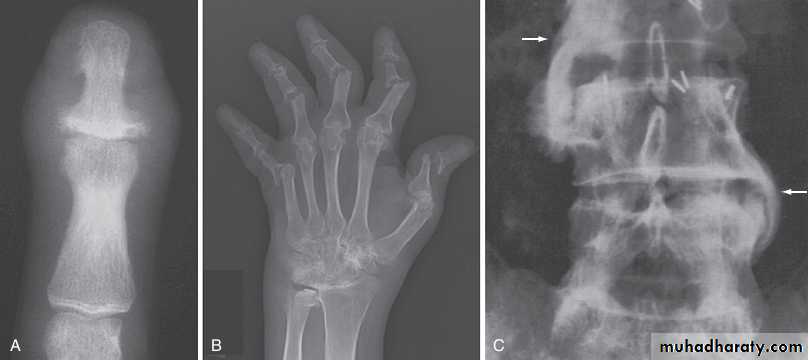

In chronic or recurrent disease, X-rays show joint space narrowing and proliferative erosions.Another characteristic feature is periostitis, especially of metatarsals, phalanges and pelvis, and large, ‘fluffy’ calcaneal spurs.

In contrast to AS, radiographic sacroiliitis is often asymmetrical and sometimes unilateral, and syndesmophytes are predominantly coarse and asymmetrical, often extending beyond the contours of the annulus (‘nonmarginal’)

X-ray changes in the peripheral joints and spine are identical to those in psoriatic arthritis.

X-rays may be normal or show erosive change with joint space narrowing. Features that favour PsA over RA include the characteristic distribution of proliferative erosions with marked new bone formation, absence of periarticular osteoporosis .

Imaging of the axial skeleton often reveals features similar to those in chronic reactive arthritis, with coarse, asymmetrical, nonmarginal syndesmophytes and asymmetrical sacroiliitis.